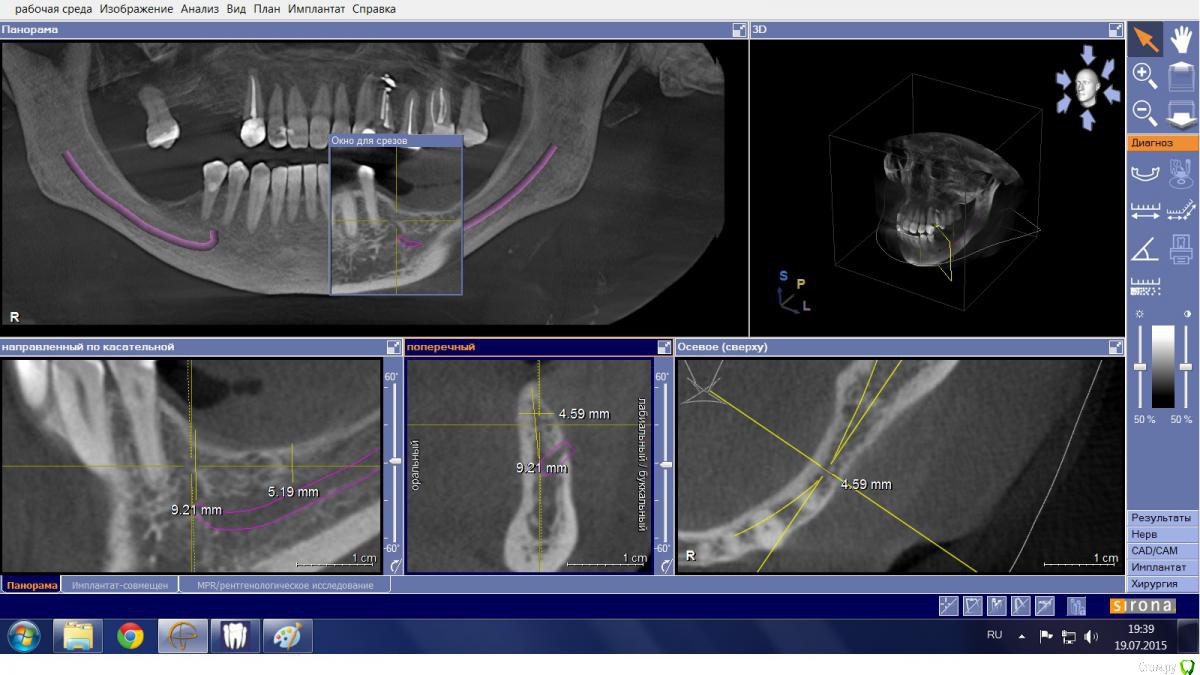

Mario Опубликовано 19 июля, 2015 Поделиться Опубликовано 19 июля, 2015 Здравствуйте, доктора, есть пациентка, категорически не желающая носить съемный протез и опыта такого не имеющая. Думал в сторону "крыши", но тут где-то ILGAMSA, кажется, писал, что не менее 5 мм крыша + 1 мм до канала, иначе резорбция. Латерализацию не рассматривал ввиду отсутствия соответствующего скилла. Какие еще могут быть варианты? Ссылка на комментарий

Mario Опубликовано 19 июля, 2015 Автор Поделиться Опубликовано 19 июля, 2015 Лучше отвертикалитьширина гребня в области 35 позволит? Ссылка на комментарий